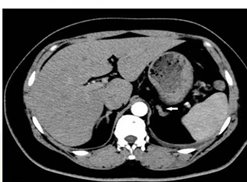

对于肾上腺腺瘤的诊断,需要综合运用多种检查手段。实验室检查如激素水平测定,有助于判断肿瘤是否具有功能性以及分泌的激素类型。影像学检查,如CT、MRI等,能够清晰地显示肿瘤的位置、大小、形态等特征,为诊断和治疗提供重要根据。

如果体检发现肾上腺腺瘤,首先要明确它是否“有功能”:通过CT或MRI明确腺瘤的大小、位置、形态,帮助判断性质。

肾上腺CT正常表现

1.形态:形态各异;右侧:斜线状、倒“V”、倒“Y”形;左侧: 倒“V”、倒“Y”形或三角形;三维重建呈叶状。

2.大小: 侧支厚度<10mm;侧支厚小于同侧膈肌脚,面积小于150mm。

3.密度: 均匀,边缘光滑,无外凸结节。

4.强化: 均匀,边缘光滑。

肾上腺腺瘤CT表现

1.肾上腺腺瘤发生于肾上腺皮质,含脂质;

2.直径多小于3cm;

3.CT值<10HU;

4.出血、坏死、囊变少见;5.CT增强:早期快速廓清